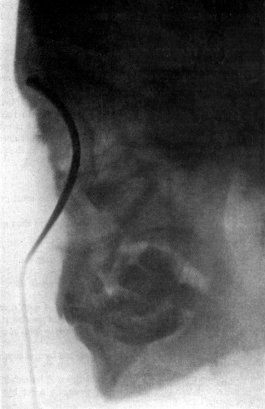

| 267. | Skiagram showing an Angular Tracheotomy Tube in the Trachea | 518 |

| 268. | Anatomy of the Larynx and Trachea and the Position of Incisions for the Operations in this Region | 525 |